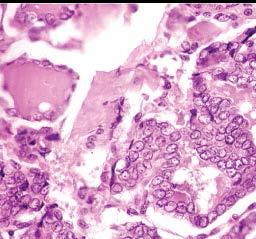

this is the most common malignancy of the thyroid gland (85%) , resulting from activation of the MAP kinase pathway, and is not aggressive so carries an excellent prognosis

papillary thyroid

*note that some of the cells look like they are empty of nuclei